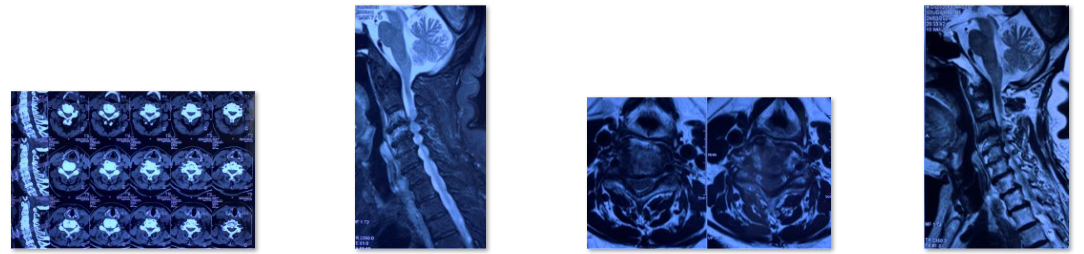

颈椎管狭窄症也是中老年人常见脊柱疾病,在椎管狭窄症发病率中仅次于腰椎管狭窄症。颈椎管狭窄症:构成颈椎管各解剖结构因发育性或退变因素造成骨性或纤维性退变引起一个或多个节段官腔狭窄导致脊髓血液循环障、脊髓及神经根压迫症者为颈椎管狭窄症。主要症状为1.感觉障碍:四肢麻木、过敏或疼痛,胸腹骨盆区发紧(束带感),严重者可有呼吸困难;2.运动障碍:四肢无力、僵硬不灵活,多数有下肢无力沉重、脚落地似踩棉花感,站立不稳,加重可出现四肢瘫痪;3.大小便障碍。颈椎管狭窄症患者CT或MRI通常表现为多节段颈椎间盘突出、黄韧带增生肥厚,颈椎椎管容积大大减小,脊髓多节段受压。

术前